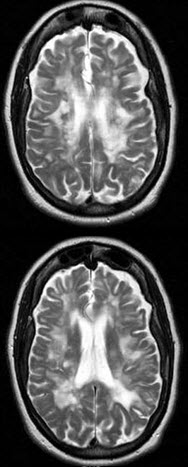

女,56岁,既往有癫痫病史,请结合CT图像选择最可能的诊断()

A .多发性硬化

B .脑出血

C .脑梗死

D .颅脑肿瘤

E .正常脑实质

女,56岁,既往有癫痫病史,请结合CT图像选择最可能的诊断()

[单选题]女,56岁,既往有癫痫病史,请结合CT图像选择最可能的诊断()A . 多发性硬化B . 脑出血C . 脑梗死D . 颅脑肿瘤E . 正常脑实质

女,56岁,有癫痫史,结合CT图像,最可能的诊断是()

[单选题]女,56岁,有癫痫史,结合CT图像,最可能的诊断是()A . 多发性硬化B . 脑出血C . 脑梗死D . 颅脑肿瘤E . 正常脑实质

女,56岁,有癫痫史,结合CT图像,最可能的诊断是()

[单选题]女,56岁,有癫痫史,结合CT图像,最可能的诊断是()A .多发性硬化B .脑出血C .脑梗死D .颅脑肿瘤E .正常脑实质